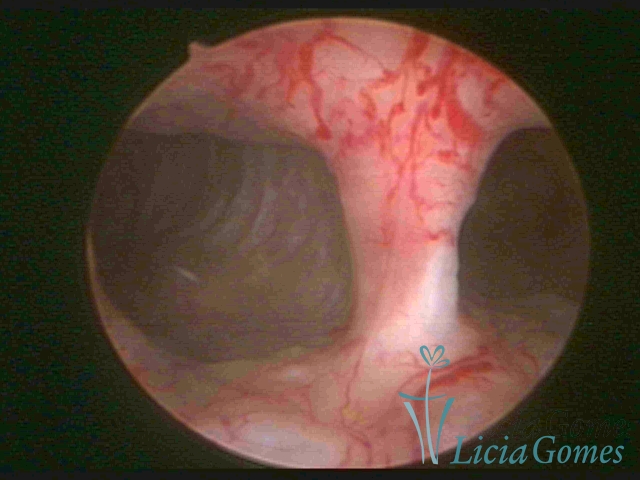

Uterus didelphys

The presence of two uterine cervices and a double vagina, similar to unicornuate uteri, with a normal covering of endometrium.